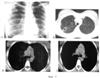

Сущность предлагаемого изобретения представлена на фиг.1, 2 и 3. На фиг.1 – данные рентгенологического обследования больного (пример 1), на фиг.2 и 3 – данные рентгенологического обследования больного (пример 2).

При рентгенологическом обследовании в момент поступления (Фиг.2-А, Б) определяется в верхней доле правого легкого на фоне разнокалиберных очагов полость распада (каверна) диаметром 1,8 см с неравномерно утолщенной стенкой. При СКТ (Фиг.2-В, Г) дополнительно визуализируются увеличенные лимфоузлы нижней правой паратрахеальной и бифуркационной группы до 1, 2 см. Структура лимфоузлов не изменена.

При контрольном СКТ обследовании через 2,5 месяца (Фиг.3-А, Б, В, Г) отмечается закрытие полости деструкции с трансформацией его в казеозно-некротический фокус размером 1, 2 см, с рассасыванием значительной части очагов вокруг. Регрессия размеров лимфатических узлов нижней правой паратрахеальной и бифуркационной группы до 0,6 см. На основании отсутствия тенденции к слиянию в конгломераты и изменения структуры лимфатических узлов сделан вывод о реактивном характере гиперплазии, что подтверждается быстрой регрессия со стороны лимфатических узлов.